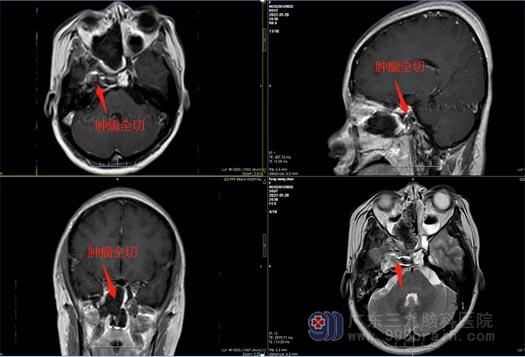

找到广东三九脑科医院副院长鲁明后,经我院专业检查,初步诊断为脑膜瘤,该部位的脑膜瘤以眼的症状为主。考虑患者年轻,既要切除病灶,同时也要保护好神经功能,如何以最小的创伤解决患者的问题,鲁明带领神经外五科王国良主任团队进行了讨论。

最后一致决定采用“内镜辅助下经鼻行右侧鞍旁海绵窦内占位性病变切除术”,不用开颅,从鼻孔进入。内镜下见肿瘤呈灰白色,质软,全切肿瘤,手术顺利结束。术后,小方视物重影消失,未出现术后并发症,一周后满意出院。